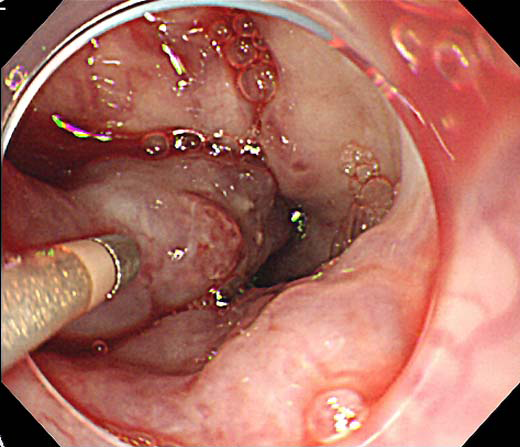

胃静脈瘤の内視鏡所見

胃噴門部から穹窿部に結節状の血管拡張を認める。